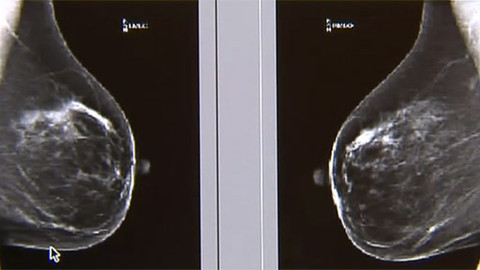

Historie i přítomnost radiologie — Intervenční radiologie a hluboká žilní trombóza — Antikoncepce